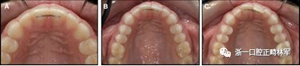

圖3.極軟弓絲完全完好,在多個(gè)空間平面上的拱形歪斜,右側(cè)尖牙的面部傾斜以及右側(cè)側(cè)切牙和中切牙在相反方向上的扭矩:A,頰面視圖; B,咬合面視圖。